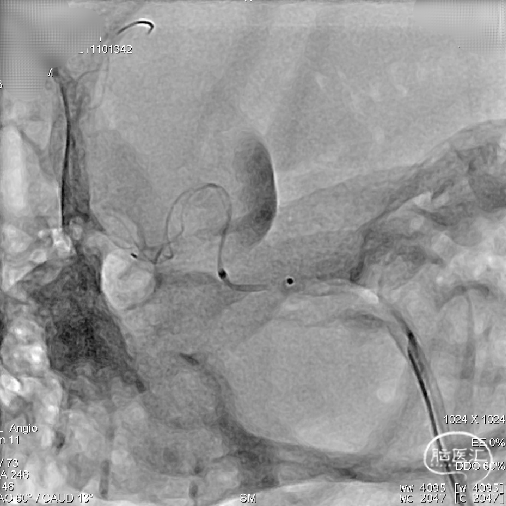

路图显示患者颈内动脉血管迂曲,瘤口处载瘤动脉呈现”S”反角弯;为使支架导管能顺利到达动脉瘤远端区域,采用囊内“成襻/解襻技术”,通过交换导丝带栓塞微导管到达动脉瘤远端,交换Fastrack-27支架微导管到达M1段。

输送支架到达支架微导管远端,缓慢回撤Fastrack-27支架微导管使支架头端打开呈“V”型,整体回撤支架系统定位于颈内动脉分叉段下约2mm位置进行锚定。

因载瘤动脉较为迂曲,为使支架头端锚定牢固, 4.5mmx45mm Tubridge血流导向密网支架前端1/3处采用稳定支撑系统逐步缓慢给张释放支架,使支架前端充分打开并与血管壁充分贴合。

当Tubridge血流导向密网支架释放到瘤颈弯段位置时,既要保障支架能充分打开、又要保障近端导管张力可控防止支架整体疝入动脉瘤囊内。因此采用节段性“推拉释放技术”既局部给张/松张,来回推挤技术释放支架,并通过持续造影观察支架打开、贴壁及血流转向效果等情况。

通过减影、显影所示,4.5mmx45mm Tubridge血流导向密网支架尾端长度充分且足够,为达到预设计的释放落脚点位置,支架尾端释放采用“推挤+减张瞬间释放技术”通过支架张力使尾端快速打开。